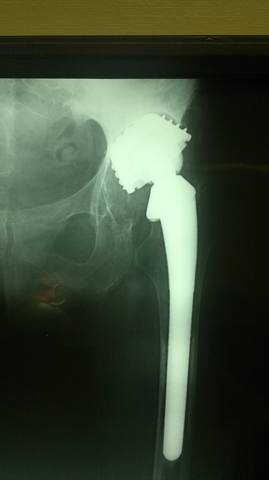

Здравствуйте, дорогие читатели нашего форума!<br /><br />Эндопротезирование при дегенеративно-дистрофических заболеваниях, а также травмах и их последствиях остается актуальным, бурно развивающимся направлением в современной ортопедии. С каждым годом в мире увеличивается число лиц нуждающихся в выполнении подобного рода операций. <br /><br />Замена собственного сустава искусственным позволяет огромной категории больных избавиться от хронического болевого синдрома, восстановить объем движений и функцию пораженного сустава, вернуться к своей профессиональной деятельности. <br /><br />В то же время известно, что каждый эндопротез имеет свой определенный "срок службы", длительность которого зависит от целого ряда обстоятельств. С одной стороны  это качество материалов, применяемых для изготовления имплантатов, с другой - особенности пациента и т.д.<br /><br />С увеличением пула пациентов, которым была выполнена первичная операция, возрастает нуждаемость  в так называемом "ревизионном эндопротезировании". Актуальность темы обусловлена тем, что хирург сталкивается при ревизии с уже не обычной ситуацией, в которой анатомические ориентиры часто бывают разрушены.<br /><br />В тему предлагаю выкладывать реальные клинические случаи и примеры ситуаций, с которыми сталкивается ортопед при ревизионном эндопротезировании.<br /><br />Начну с двух случаев. <br /><br />Первый: женщина, 80 лет, срок службы тотального цементного эндопротеза тазобедренного сустава 19 лет.<br /><br /> <br /><br /> <br /><br />Второй:<br /><br />женщина, 64 года, тотальный безцементный эндопротез тазобедренного сустава, срок службы 15 лет:<br /><br /> <br /><br />Третий:<br /><br />женщина, 60 лет, тотальный цементный протез тазобедренного сустава, срок службы 10 лет:<br /><br />